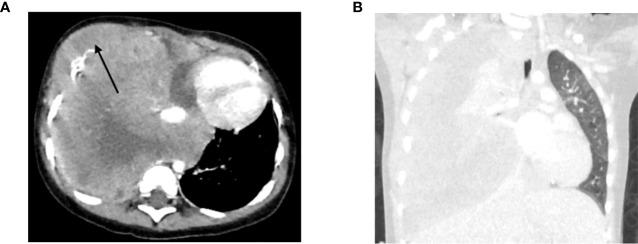

Solid tumors account for about 30% of all pediatric cancers. The diagnosis is typically based on histological and molecular analysis of a primary tumor biopsy. Liquid biopsies carry several advantages over conventional tissue biopsy. However, their use for genomic analysis and response monitoring of pediatric solid tumors is still in experimental stages and mostly performed retrospectively without direct impact on patient management. In this case series we discuss six clinical cases of children with a solid tumor for whom a liquid biopsy assay was performed and demonstrate the potential of liquid biopsy for future clinical decision making.

In three patients cfRRBS helped to establish the diagnosis of a rhabdomyosarcoma, an Ewing sarcoma and a neuroblastoma (case 1-3). In two patients, liquid biopsies were used for prognostication, by MYCN ddPCR in a patient with neuroblastoma and by RT-qPCR testing rhabdomyosarcoma-specific mRNA in bone marrow of a patient with a rhabdomyosarcoma (case 4 and 5). In case 6, mRNA testing demonstrated disease progression and assisted clinical decision making.